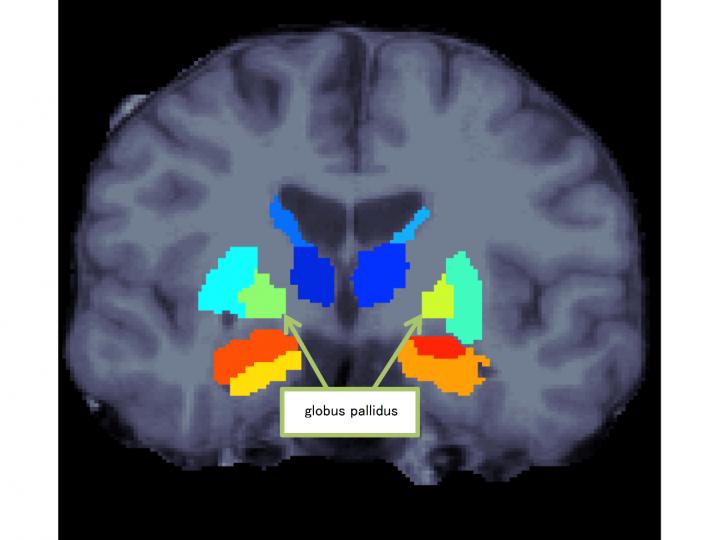

A research group led by Ryota Hashimoto, an associate professor at Osaka University, Naohiro Okada, a graduate student at the University of Tokyo, and Kiyoto Kasai, a professor at the University of Tokyo, replicated prior findings that the volume of globus pallidus (one of the basal ganglia in the brain) in schizophrenia was larger than that in healthy subjects. Also, the group found that patients with schizophrenia demonstrated a specific leftward volumetric asymmetry for the globus pallidus.

They compared and analyzed magnetic resonance imaging (MRI) brain images of 1,680 healthy individuals and 884 patients with schizophrenia from 11 research institutes participating in Cognitive Genetics Collaborative Research Organization (COCORO), and examined the differences between schizophrenia and healthy controls in the subcortical regional volumes and their asymmetries.

Compared to controls, patients with schizophrenia demonstrated smaller bilateral hippocampus, amygdala, thalamus and accumbens volumes as well as intracranial volume, but larger bilateral caudate, putamen, pallidum and lateral ventricle volumes. Also, patients with schizophrenia demonstrated a specific leftward asymmetry for globus pallidus volume.

These results suggest the possibility of aberrant laterality in neural pathways and connectivity patterns related to the globus pallidus in schizophrenia. Further, through the elucidation of the underlying pathological mechanisms, it will be a step toward the development of therapeutic strategies for schizophrenia.